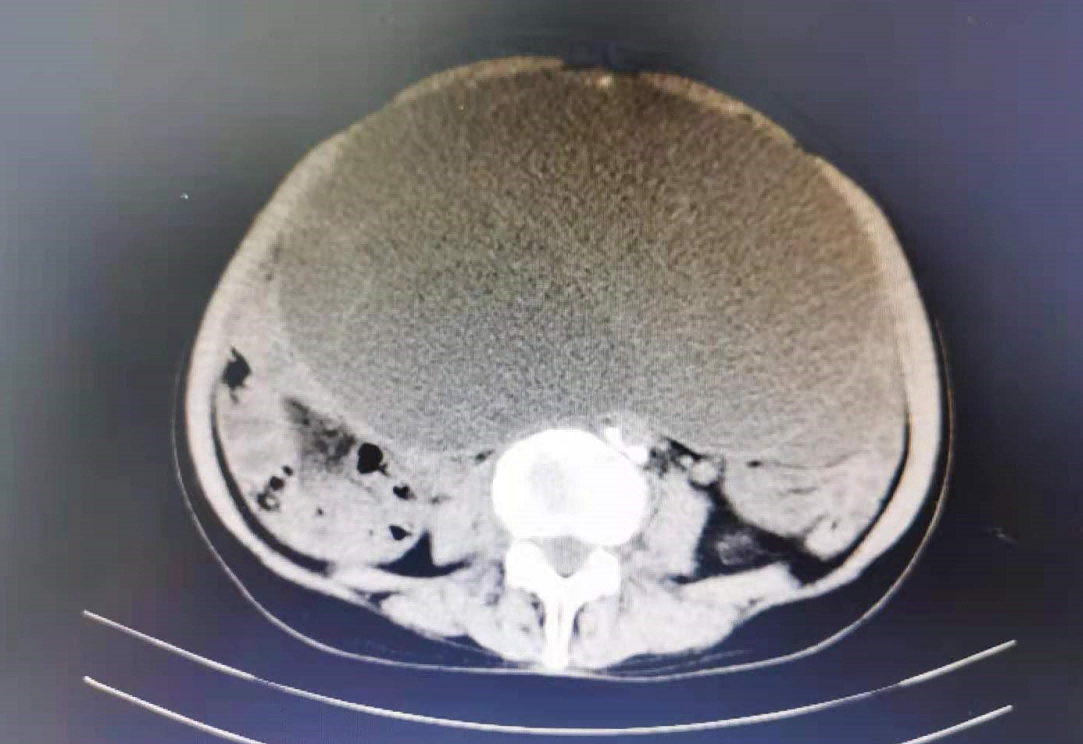

患者高妈妈,今年70岁,因“发现腹部包块伴胀痛2月”来到彭水县医院外三科住院治疗。完善检查后,发现高妈妈的情况较为复杂,患者70岁高龄,腹盆腔巨大肿瘤,同时合并左肾囊肿;肝脏多发钙化灶;冠状动脉硬化;肺炎间质性改变……鉴于此,特请妇科会诊,山东支医专家张丽丽副主任医师和本院高琼主治医师接到会诊后立即前往病房,对患者行综合评估后,考虑卵巢肿瘤可能性大,遂转入妇科继续治疗。

转入妇科第3天,高妈妈终于迎来了她的卵巢肿瘤切除手术。手术全程由手术室麻醉科保驾护航,张丽丽主任主刀施术,凭借丰富的手术经验,轻柔娴熟的操作,顺利摘除了高妈妈体内的一重约10+斤、直径约30cm的巨大肿瘤。手术过程顺利,出血量极少。但术中亦有惊险一幕,手术伊始,高妈妈突然出现血压一度升高,心律失常,ST段抬高,考虑有心肌缺血改变,麻醉科医师紧急处理,予以尼卡地平降压,查心肌酶谱及血气分析均无异常,生命体征恢复平稳,术毕,高妈妈于麻醉清醒后安返病房。

术后病理检查证实,高妈妈的卵巢肿瘤是卵巢粘液性囊腺瘤,属于良性肿瘤。经过术后康复治疗和精心的护理,术后第6天,高妈妈开心地出院了。